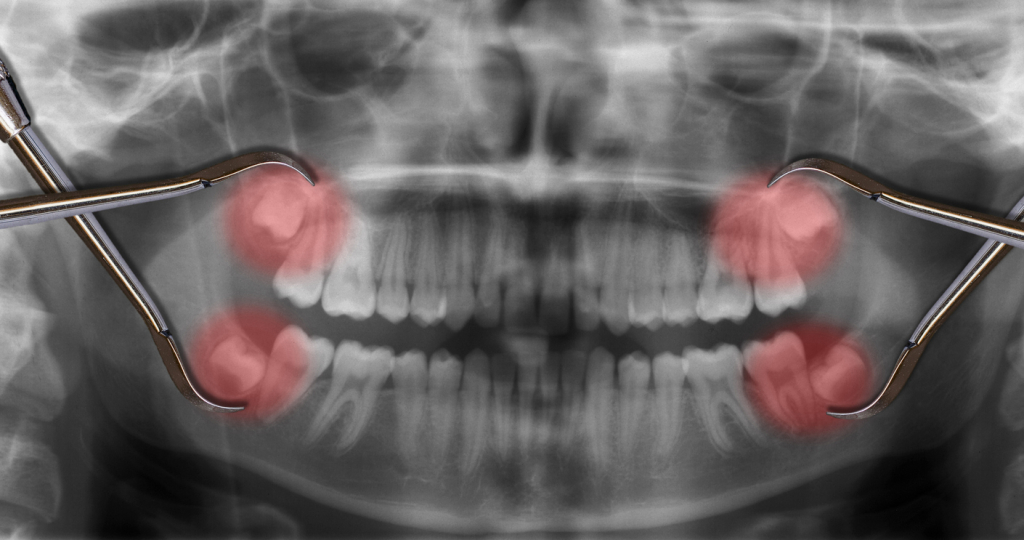

Egy ki nem nőtt, vagy félig nőtt bölcsességfog számos nehézséget okozhat az egyén számára. Az ilyen fog gyakran a szájüreg hátsó részén elakad, mivel az állkapocs nem tudja befogadni. Ennek eredményeként nyomást gyakorol a szomszédos fogakra, ami fájdalmat és elmozdulást eredményezhet.

Továbbá, a ki nem nőtt bölcsességfog ideális táptalajt biztosít a baktériumok számára, mivel nehezen tisztítható területet hoz létre. Ez ínybetegségekhez és fogszuvasodáshoz vezethet, amelyek hosszú távon komoly komplikációkat okozhatnak. Olvass még a témában